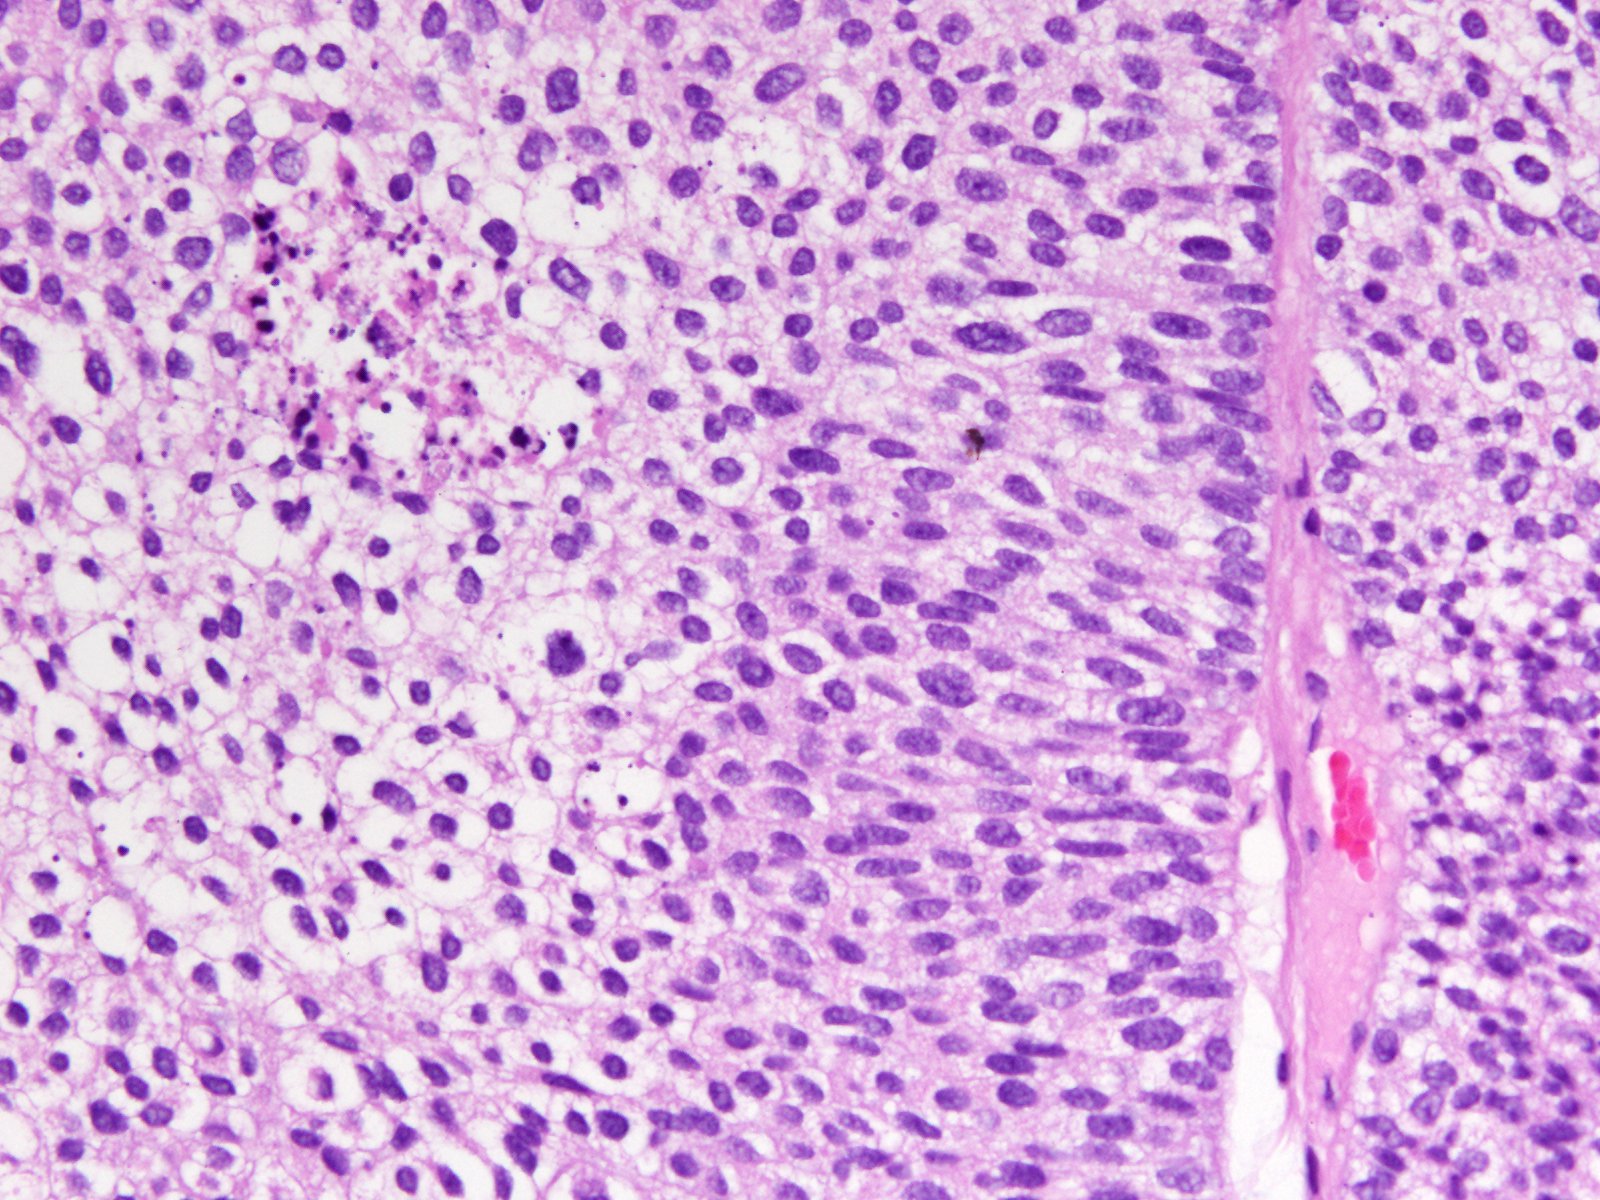

Consensus grade: High-grade papillary urothelial carcinoma (HG-PUC)

| Pathologist 22 | High-grade papillary urothelial carcinoma (HG-PUC) | Bordering on higher |

Mixed LG and HG. Diagnosis based on HG. |

Case description (by case creator):

Papillary tumor in TUR-BT.